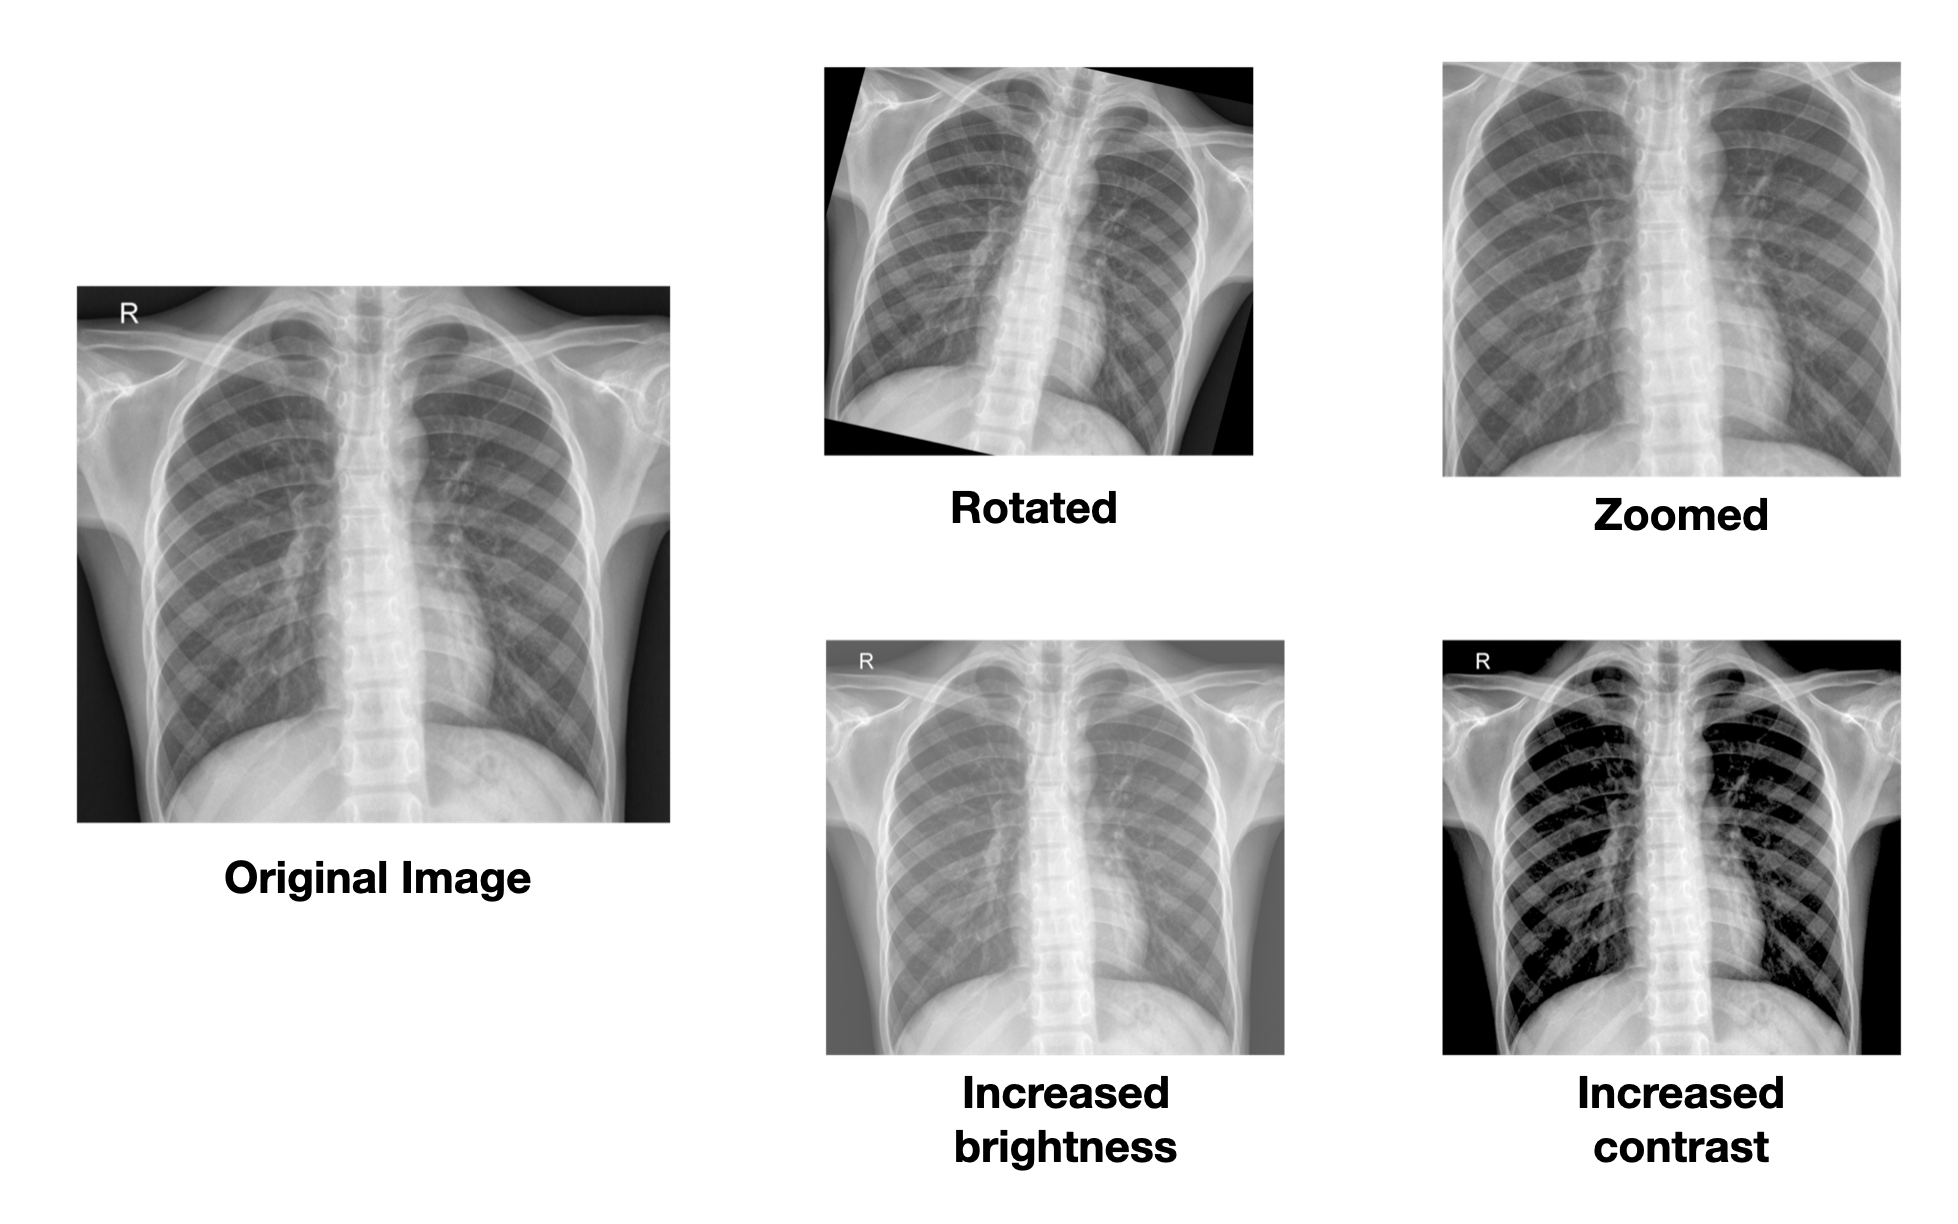

256 x 256)Examples of different data augementation techniques. Source: [2]